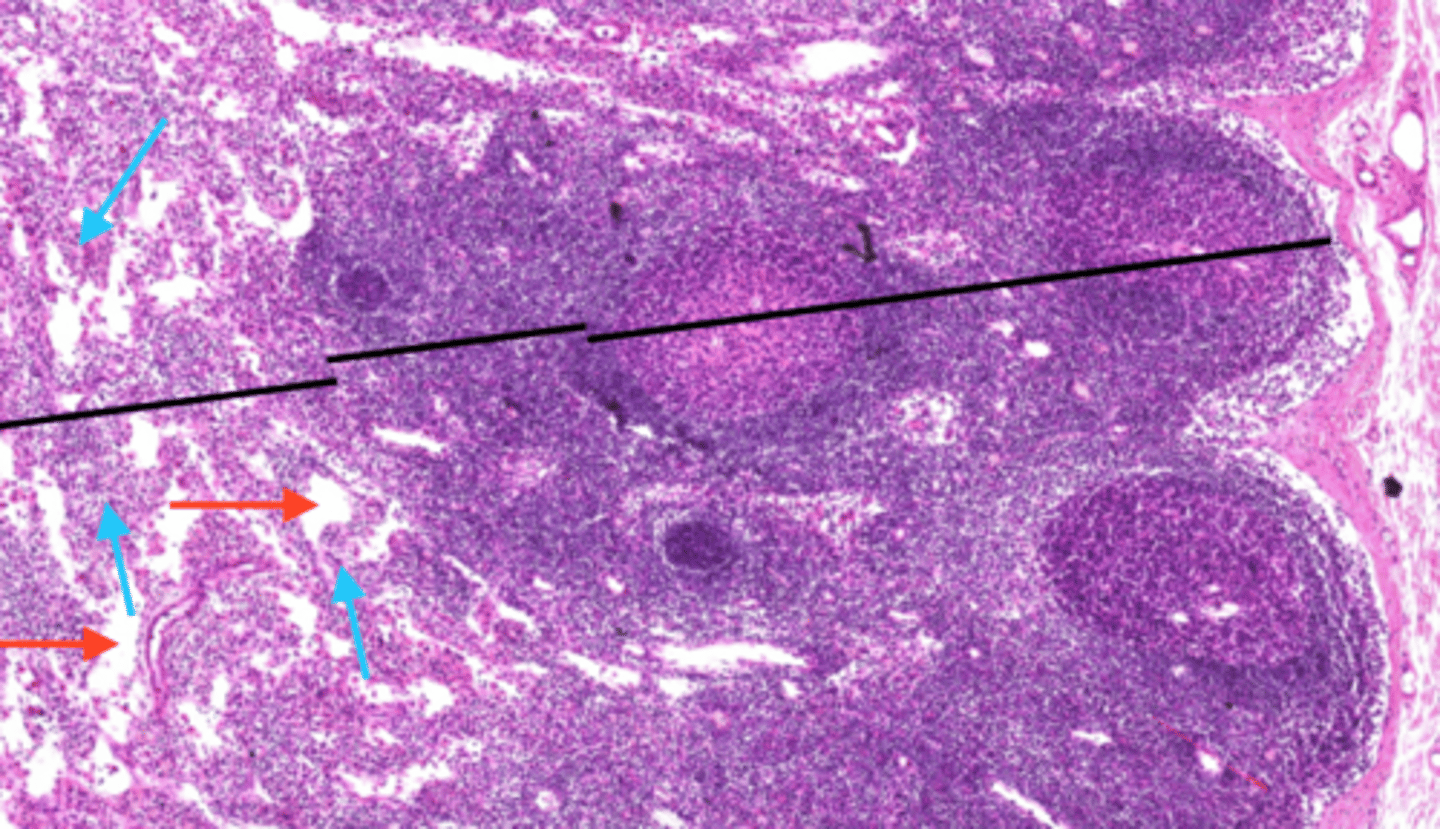

red pulp (spleen)

-is the dark red tissue in the spleen containing sinusoidal capillaries, connective tissue fibers, and immune cells like macrophages, plasma cells, and lymphocytes.

-It destroys old red blood cells, removes pathogens and toxins

-facilitates lymphocyte movement between splenic tissue and blood.

white pulp (spleen)

has whitish appearance in a fresh spleen. Lymphocytes, macrophages surrounding small branches of splenic artery